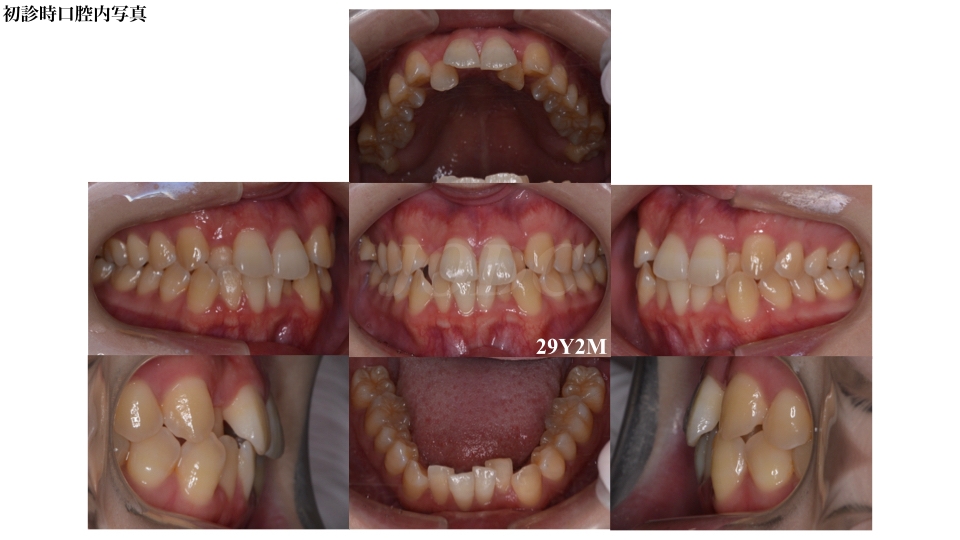

叢生

過蓋咬合